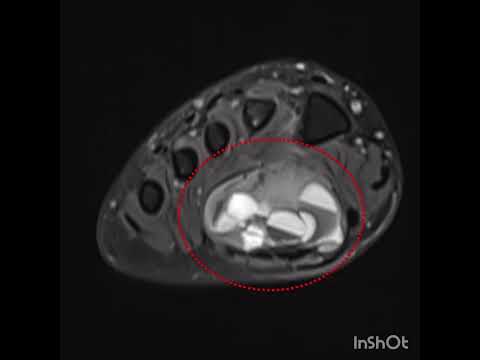

Kemik tümörlerinin tanısında basit röntgenler çok önem taşır ve doğru şekilde değerlendirildiğinde yeterli olabilir. Ancak kötü huylu olabileceği düşünülen ya da yumuşak doku tümörlerinde mutlaka MR çekilmelidir. MR kontrastlı olmalı ve yeterli kalitede olacak şekilde çekilmelidir. Aksi halde hasta tekrar MR çektirmek zorundadır. Kemik tümörlerinde zaman zaman bilgisayarlı tomografiden de yararlanılır. Ayrıca kemik taraması isteniyorsa, ya da tümörün diğer kemiklere yayılıp yayılmadığının anlaşılabilmesi için kemik sintigrafisi de önem taşır. PET ise son derece özel bir görüntüleme yöntemi olup henüz tanı almamış hastalar için yeri yoktur.